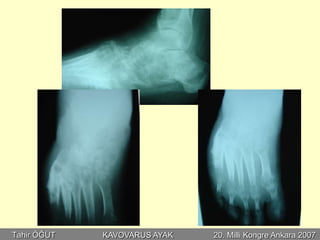

F.Y. 42, K

EMG (ileti): Normal

•Perkütan aşilotomi

•Plantar fasya gevşetme

•Metatars osteotomisi

•Jones prosedürü

•Peroneus longus transferi